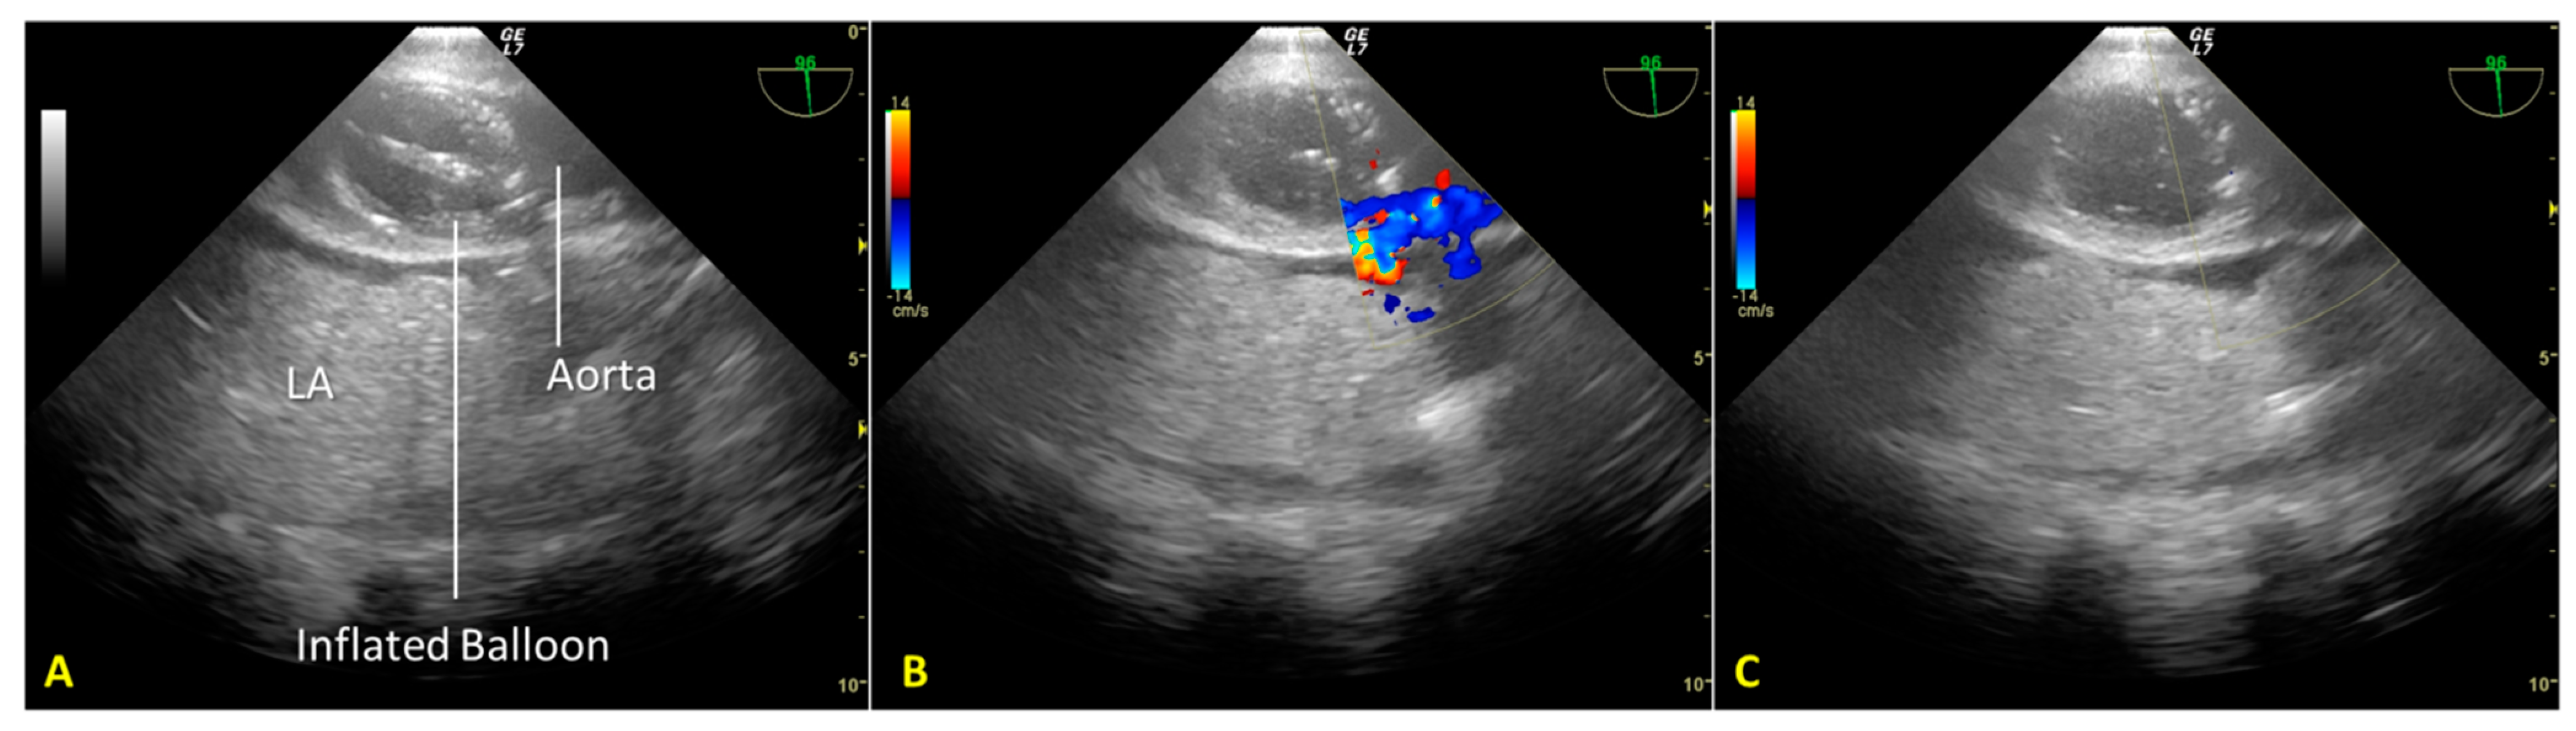

We used an introducer needle to insert a Super Stiff guidewire into the right femoral vein until the right atrium. Correct positioning of the guidewire was verified in real time using the TEE mid-esophageal bicaval view (Figure 1A). Next, we inserted a second guidewire through the right femoral artery sheath and introduced it up to the thoracic aorta. After visualizing the wire’s tip within the thoracic aorta using the mid-esophageal descending aorta short-axis view, we partially withdrew the guidewire so that its tip stopped below the diaphragm. These two guides allowed the introduction of venous and arterial A-NRP cannulae post-mortem.

Finally, we introduced a third guidewire through the left femoral artery sheath to allow proper stent placement for aortic occlusion. TEE use guided and monitored correct positioning using the mid-esophageal descending aorta long-axis view (Figure 1B,C). Using fluoroscopy, we double-checked the proper positioning of the guides and aortic occlusion catheter (AOC).

Figure 1. (A). Mid-esophageal bicaval view. The guidewire (*) was inserted through the inferior vena cava into the right atrium. (B). Mid-esophageal descending aorta long-axis view. The aortic occlusion catheter is visualized in the thoracic aorta; the deflated balloon is located just above the diaphragm. (C). Mid-esophageal descending aorta long-axis view during A-NRP. The position of the AB (inflated) remained unchanged above the diaphragm. IVC—inferior vena cava; RA—right atrium; SVC—superior vena cava; * guidewire; Ao—aorta; AOC—aortic occlusion catheter; LA—lung atelectasis; Dia – diaphragm; DB—desufflated balloon; IB—inflated balloon.